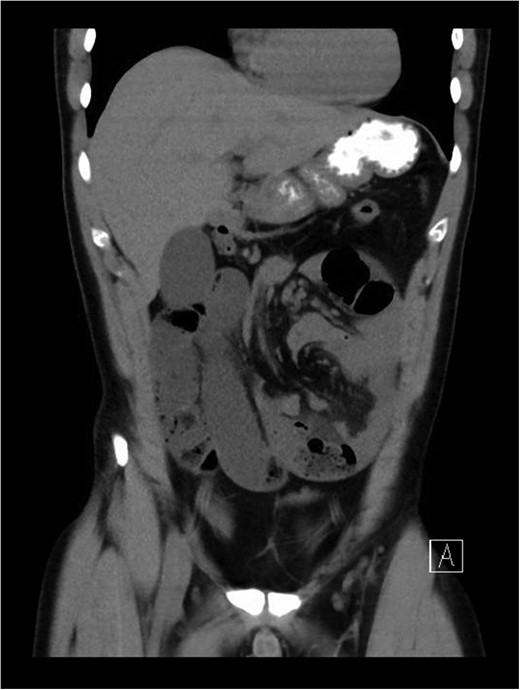

The patient was taken to the operating theatre within 1 h of arrival to the tertiary hospital. Intraoperatively, a midline laparotomy incision was created. Findings were that of distended dusky looking loops of small bowel leading to a large hernia sac in the left hemi-peritoneal cavity, with ~100 cm of jejunum and ileum in a closed loop (Fig. 3). The collapsed small bowel in the sac was carefully reduced, with no visible bowel wall compromise. The sac also contained serous fluid and was found to arise in continuity with the proximal jejunal mesentery. Once the bowel loops were reduced, and rotated back to its natural orientation, the excess membrane was then dissected and the remaining was plicated to the healthy mesentery. In addition, a short healthy mesenteric pedicle was also noted, however, there was strong pulsation from the superior mesenteric vessels. Bowels were thoroughly inspected and deemed healthy, therefore, no resection was required, and the abdominal incision was closed by layers. The patient was discharged from hospital on Day 4 post operatively with uneventful recovery period.

Intra-operative picture post exteriorizing of defect and obstructed small bowel, showing the transmesenteric hernia, covered with thin mesenteric membrane prior to reduction of incarcerated small bowel.